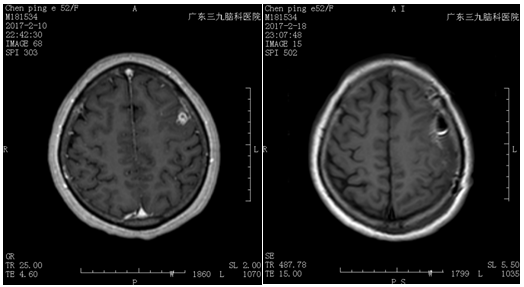

↑手术前后对比

神经外二科林涛主任和张旭标医生对该患者在外院核磁共振的影像进行分析,高度怀疑是颅内寄生虫感染。随后,学科为该患者制定了详细的手术方案。手术由神经外二科主任林涛主刀完成,在全程术中导航和电生理监测下为患者实施行了寄生虫取出术,术中在左侧额叶发现一条长约9厘米的白色裂头蚴,虫体是术中还在不断活动,完整取出虫体后,电生理提示脑功能保护完好。目前患者康复良好出院。